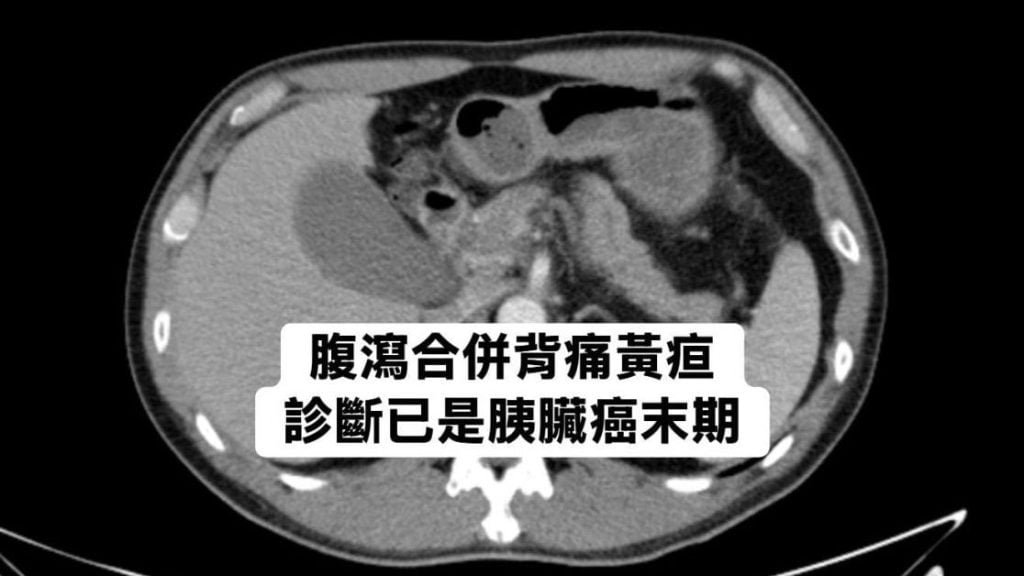

腹泻腰酸别轻忽 男子确诊胰脏癌末期

一名55岁男子近期频繁腹泻,感觉右侧腰背发酸,原以为是肠胃问题,就医抽血后发现有黄疸及胰脏发炎,进一步断层扫描发现胰脏头部肿瘤已侵犯胆管,并转移至肝脏,最终确诊为第4期胰脏癌。